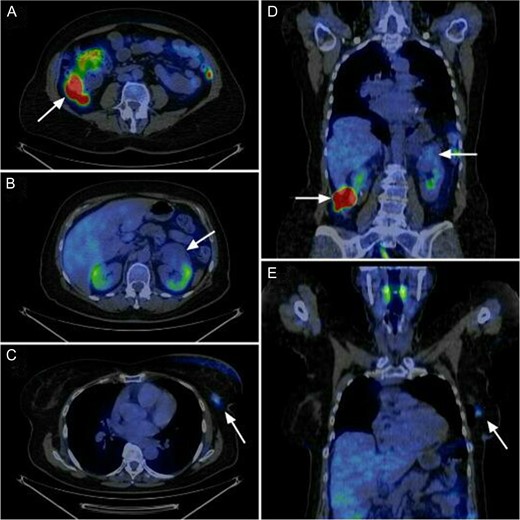

The present case is of a 70-year-old female patient with positive family history of leukaemia, colon cancer and type 2 diabetes mellitus. In the annual breast cancer screening, the mammography revealed a 1.7 cm × 2.5 cm mass in the upper outer quadrant of her left breast with axillary lymph node metastasis. Core biopsy confirmed invasive breast carcinoma (IBC) with low-grade ductal carcinoma in situ (DCIS), oestrogen and progesterone receptors were both positive (ER 100%, Q-score 7–8, PR 70%, Q-score 3–4), Her2 was negative (Score 0) and Ki67 labelling index was 5%. During the staging period, positron emission tomography-computed tomography (PET-CT) scan was performed and it demonstrated an abnormal FDG uptake in the upper part of the left kidney and in the right colon too (Fig. 1). On colonoscopy, 7–8 polyps were detected and an endophytic tumour in the ascending colon. Biopsy of the latter mass revealed moderately differentiated mucinous adenocarcinoma. Computed tomography confirmed a 3.8 cm × 3.6 cm mass of the left kidney and a 5 cm mass in the right colon extending until the hepatic flexure. (Fig. 2) Percutaneous CT-guided fine needle aspiration of the left kidney showed renal cell carcinoma. The case was referred to the multidisciplinary oncological team.

Abnormal FDG uptake in the three localisation according to the sagittal and coronal view of the PET-CT. Axial view shows (A) the colon ascendens tumour, (B) the left kidney tumour and (C) the left breast tumour. Coronal view shows (D) the left kidney tumour and the colon tumour and (E) the left breast tumour.